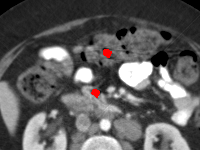

Visual comparison. As shown in Fig. 5, metallic implants such as spinal rods and hip prosthesis cause severe streaky artifacts and metal shadows, which obscure bone structures around them. cGan-CT cannot recover image intensity correctly for both cases. Sinogram domain or dual-domain methods perform much better than cGan-CT. LI, NMAR, and CNNMAR introduce strong secondary artifacts and distort the whole images. In NMAR images, there are fake bone structures around the metals, which is related to segmentation error in the prior image from strong metal artifacts. The segmentation error is also visible in NMAR sinogram. CNNMAR cannot restore the correct bone structures between rods in case 1. The tissues around the metals are over-smoothed in DuDoNet because LI sinogram and image are used as inputs, and the missing information cannot be inferred later. Our model retains more structural information than DuDoNet and generates anatomically more faithful artifact-reduced images.

Visual comparison. Fig. 7 shows two clinical CT images with metal artifacts. Case 1 is with moderate metal artifacts. cGan-CT does not suppress the artifacts completely and generates some fake details. LI, NMAR, CNN-MAR remove all the artifacts but introduce new streak artifacts, which is caused by the discontinuity in the corrected sinogram. DuDoNet outputs over-smoothed sinogram, which leads to blurred tissues close to the metal implants, such as muscle and bone. Only our model can provide realistic enhanced sinogram and remove the artifacts while retaining the structure of nearby tissues. Case 2 is very challenging as the rods bring strong metal shadows and bright artifacts around the vertebra. cGan-CT recovers the shape of vertebra but changes the overall image intensity. Other sinogram inpainting methods fail as the soft tissue and bone near the rods are heavily distorted. Our model removes part of the dark bands and reproduces correct anatomical structures around the rods.